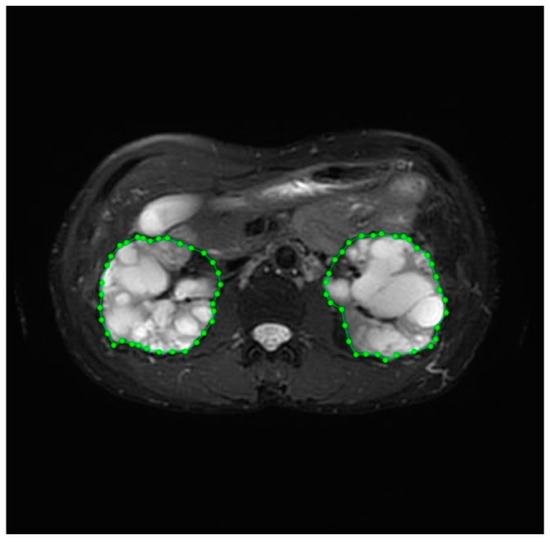

3.3. Accuracy of Segmentation